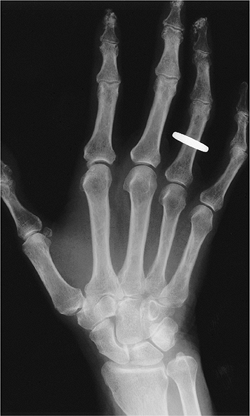

![]() |

FIGURE 13-25 Gout. Well-defined erosion with a large calcified tophus.

P.837

|

FIGURE 13-26 Gout. Swelling of the right hand and wrist with a well-defined erosion (arrow) at the fifth PIP joint.